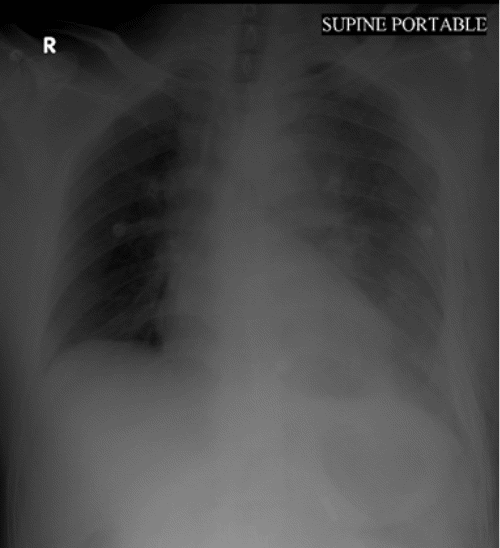

The patient was admitted to the intensive care unit (ICU) for further assessment before the surgery; his blood pressure was approximately 90/50 mmHg, and his pulse rate was 120 beats/min, which might be related to the herniated stomach inside the pericardial cavity, causing cardiac tamponade with hypotension and tachycardia. The nasogastric tube (NGT) was inserted, and approximately 300 mL (0.3 × 10-3 m3) of gastric content was aspirated. The patient felt better, which could be related to the reduction of the herniated stomach inside the abdominal cavity from the pericardial space. A few minutes later, his blood pressure increased to 105/75 mmHg, and his pulse rate decreased to 100 beats/min. A portable chest X ray film showed the absence of gastric gas in the pericardial space and NGT in the stomach (Figure 3).

Figure 3. Portable Chest Radiography Showing Absence of Gastric Gas in Pericardium After Inserting Nasogastric Tube. Published with Permission